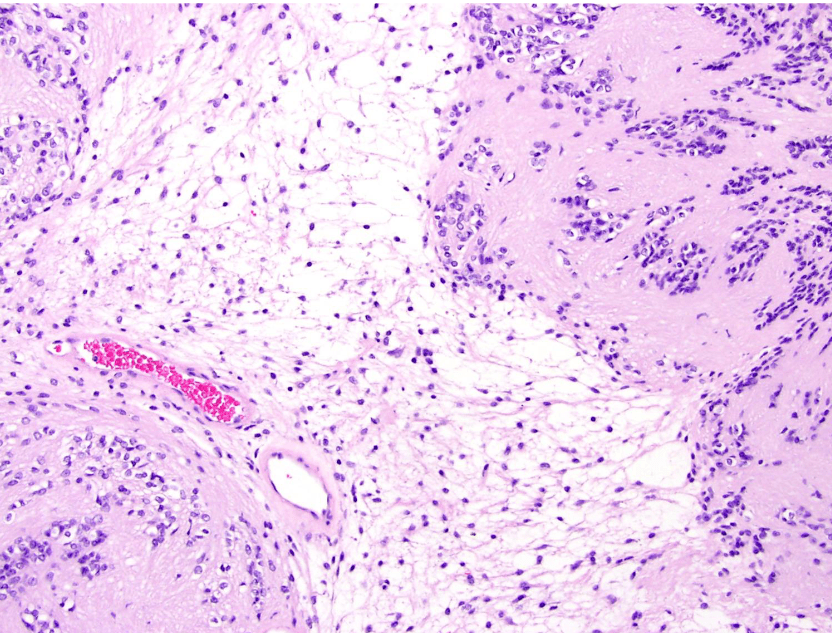

endometrial cancer